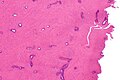

Benign bone consistent with osteoma. H&E stain.

LM benign (normal) bone

• Normal bone.